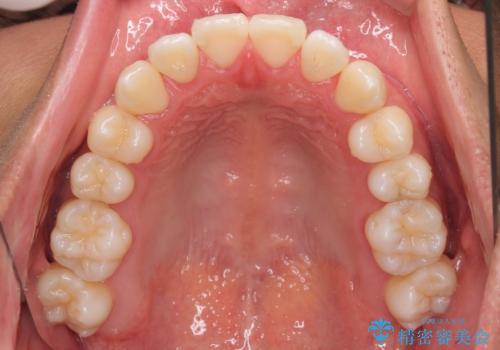

- 上下前歯部のデコボコを主訴として来院された患者様です。

上顎の歯列弓が下顎に対して狭いため、臼歯のかみ合わせがが咬頭対咬頭の状態です。

上顎の急速拡大装置を使用して、上顎骨を側方に拡大することで上顎歯列弓を拡大し、それに伴い下顎歯列弓も拡大できるようにして、歯列を整えていくこととしました。